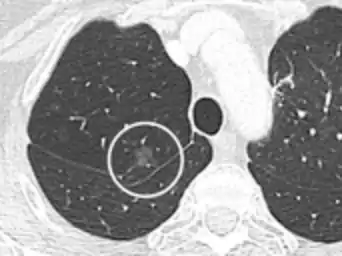

subpleural nodule.[9]

Round well-delineated solid lung nodule with smooth border.[9]